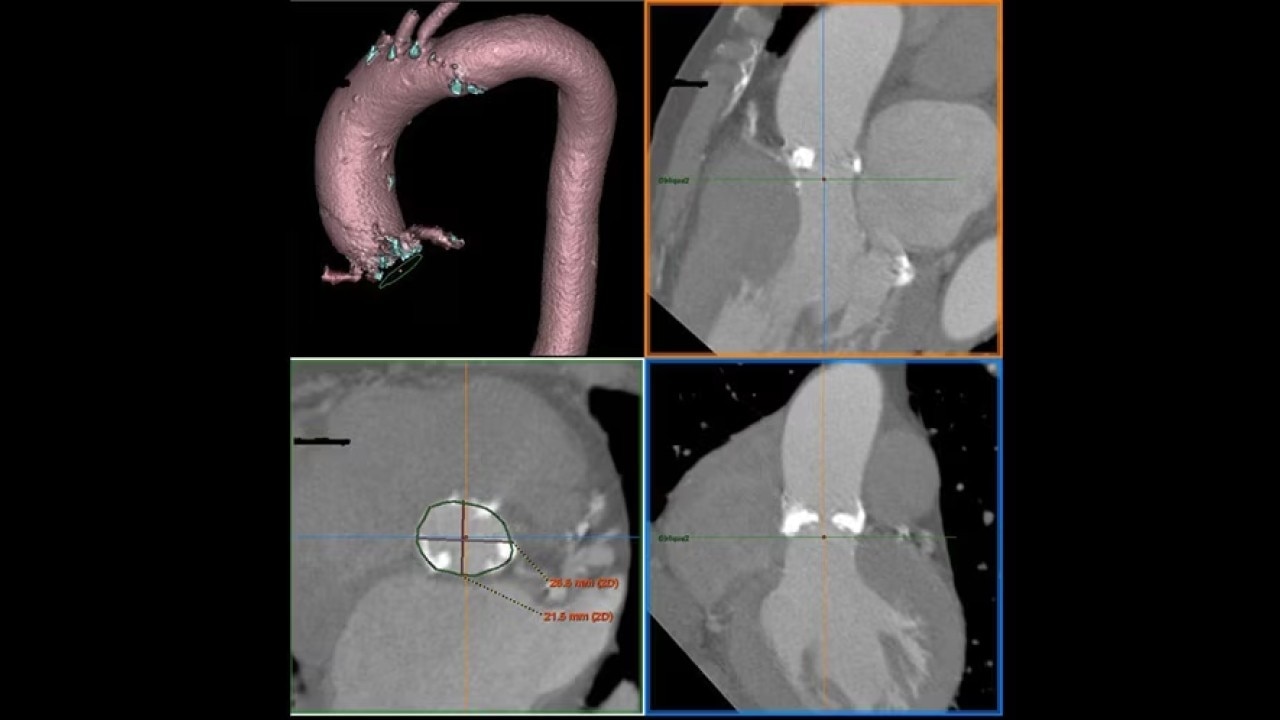

The Valve Planning protocol in the VesselIQ Xpress application lets you visualize cardiac anatomy with the degree of detail required to evaluate the presentation of the aortic valve. Armed with this information, you can develop a pre-procedural TAVR/TAVI plan to establish a therapy strategy for the patient.